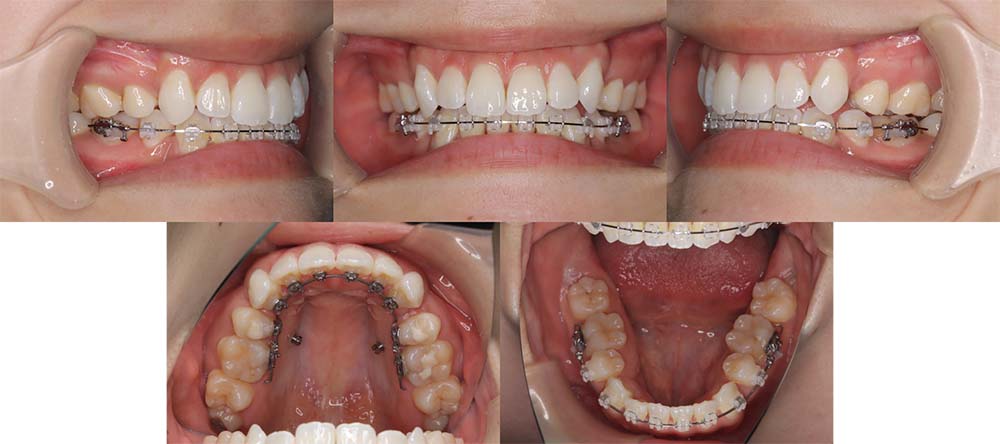

| 症例分類 | 上顎前突、叢生 |

| 診断名 | 上下叢生を伴う骨格性および歯性上顎前突 |

| 主訴 | 歯並びが悪いのが気になる、口元が気になる |

| 年齢 | 19歳5ヶ月 |

| 性別 | 女性 |

| 抜歯部位 | 上の左右第一小臼歯(2本) |

| 使用装置 | 上下裏側のワイヤー装置 |

| 治療期間 | 2年5ヶ月 |

| 保定装置 | 固定式保定装置、取り外し式保定装置(8時間) |

| 費用 |

[検査・診断料] ¥49,500 [基本施術料] ¥1,331,000 [調整料] ¥5,500/回 [抜歯] ¥5,500/本 [保定装置] ¥55,000(税込) 抜歯や虫歯治療は他院にて費用が別途かかります。(抜歯¥4,000〜10,000/本)

上顎前突で上の歯がかなり前にきているため、上顎両側第一小臼歯を抜去して治療を行いました。上の前歯をしっかりと舌側に移動しないといけないため、矯正用アンカースクリューを使用しました。また、下顎はわずかに歯の間の削合(ディスキング)を行い、初診時より歯が前方に出ないように治療を進めました。

口唇閉鎖不全もありましたが、上の前歯が舌側に移動することにより改善することができ、問題なく咬合させることができました。